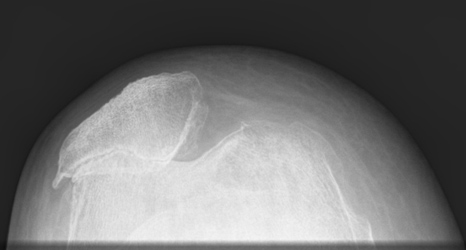

The knee is made up of the main joint between the femur (thigh bone) and tibia (shin bone) as well as the patellofemoral joint between the femur and the patella (knee cap). Often, when there is arthritis involving the patellofemoral joint, the main knee joint is also affected. Occasionally, however, there can be significant arthritis under the knee cap but the main joint is normal. In this situation, a patellofemoral joint replacement might be an option. It aims to replace the undersurface of the patella and the groove in the femur that the patella sits in but does not change the main joint.

Under an anaesthetic, a large incision is made in the front of the knee and the knee joint is exposed. The groove in the femur (trochlea groove) is reshaped and a metal replacement is cemented in place. The undersurface of the patella is then cut flat and a plastic button is cemented onto it. The plastic button can then glide up and down in the metal groove.